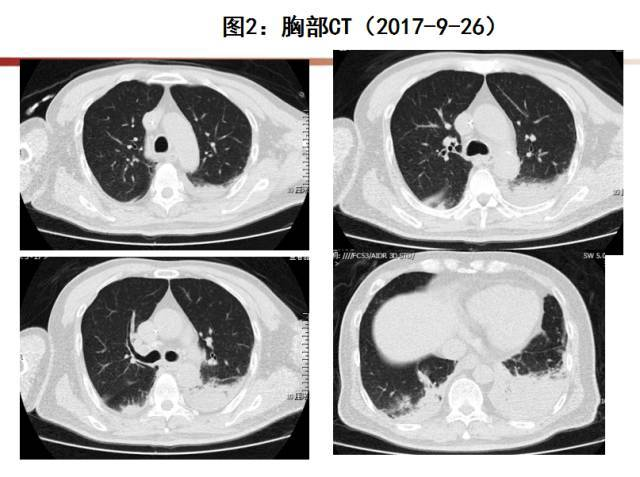

◉甲型H3N2流感病毒感染合并坏死性肺炎一例

这种情况在临床上被称为急性肺损伤(ALI)或急性呼吸窘迫综合征(ARDS)。数据显示,在重症流感患者中,约30%会发展为ARDS,而一旦进入ARDS阶段,死亡率可能高达40%-60%(数据来源:WHO)。